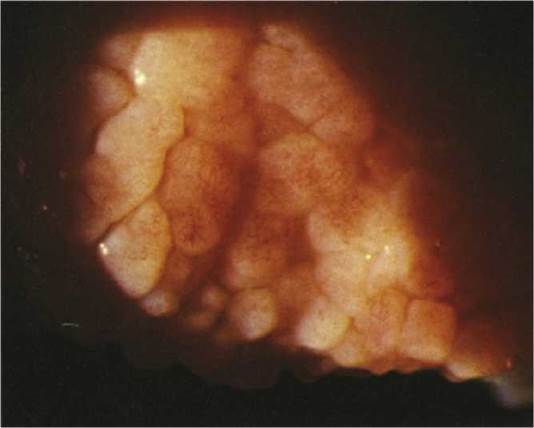

Critical. Large conjunctival papillae seen under the upper eyelid or along the limbus (limbal vernal) (see Figure 5.1.6).

FIGURE 5.1.6 Vernal/atopic conjunctivitis with large superior tarsal papillae.